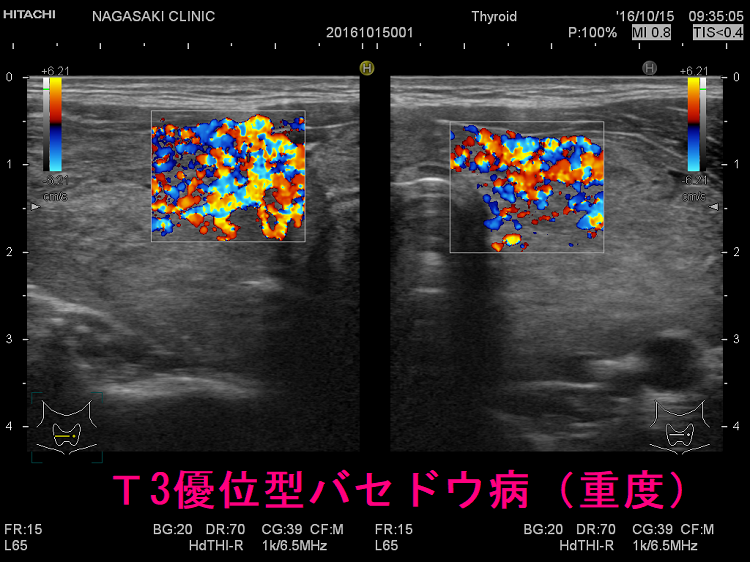

T3優位型バセドウ病の超音波(エコー)所見

ケース① 下甲状腺動脈血流速度(ITA-PSV)は異常高値

T3優位型バセドウ病 超音波(エコー)画像 ドプラーモード:下甲状腺動脈血流速度(ITA-PSV)は異常高値です。

ケース② 巨大甲状腺腫・甲状腺内部血流増大